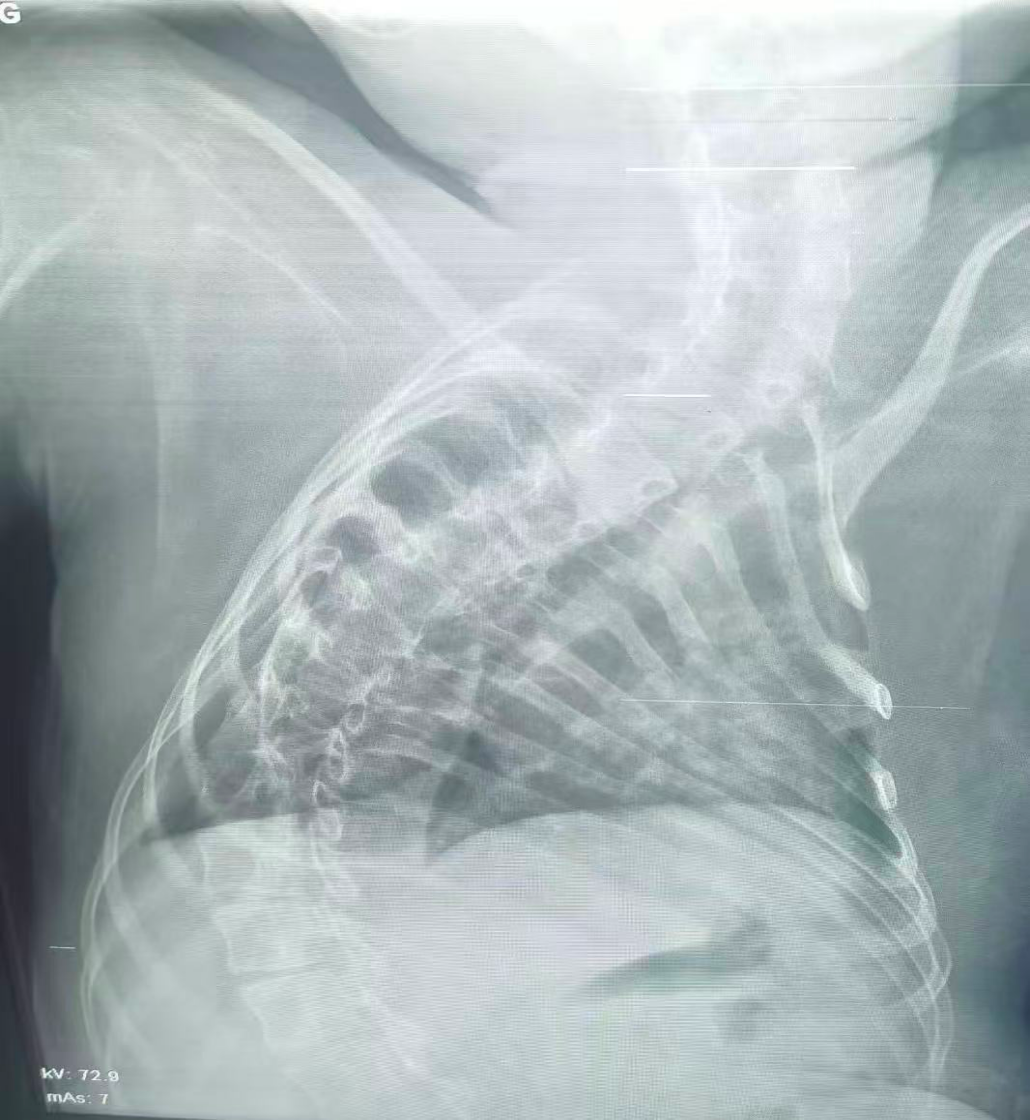

該患兒因患脊髓性肌萎縮癥長期臥床,呼吸肌已嚴重?zé)o力,自主呼吸微弱且?guī)缀鯁适Э人耘盘的芰Γ舜尾l(fā)支氣管肺炎后,肺部感染迅速加重,生命已然懸于一線。更棘手的是,嚴重的脊柱側(cè)彎使患兒胸廓畸形、氣道解剖結(jié)構(gòu)明顯移位,常規(guī)纖支鏡進鏡路徑完全失效,扭曲狹窄的氣道如同縱橫交錯的“迷宮”,每一步操作都必須精準(zhǔn)到毫米級別。

治療前

治療后